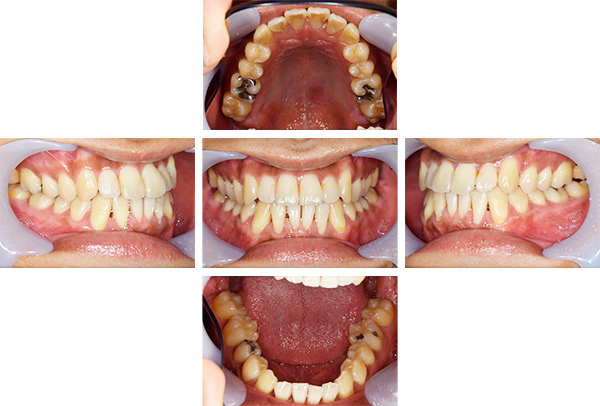

歯列矯正・インレー・クラウン症例

前歯が黒っぽいのが気になる、

悪いところは全部治したい

年齢 54代女性

主訴 歯をきれいにしたい

治療

期間

4年

費用 セラミックインレー 12本

660,000円

オールセラミックプレミアムクラウン 3本

495,000円

矯正 874,900円

計 2,029,900円(税込)

※全て税込となります。

症例写真(治療前)

担当医師所見

治療前:

八重歯が目立ちます。また銀歯もおおく、見た目が気になります。虫歯も散見できます。

症例写真(治療後)

治療後:

矯正治療と虫歯の治療すべて終わったときの写真になります。見た目も最初の頃とは全く違いますし、お口の中もすごく綺麗です。

方針

まずは虫歯の治療を行い、被せ物をする部分は仮歯をいれて矯正を行う。矯正終了後、仮歯の部分を最終的な被せ物に変えていく。また気になっていた銀歯もセラミックに変えて終了となった。

内容

セラミックインレー、オールセラミックプレミアム、矯正

虫歯の治療によって歯が一時的に染みるようになる可能性があります。また、歯を抜かずに矯正を行っていますが、全ての方で歯を抜かずに矯正ができるわけではありません。

治療リスク・副作用

・詰め物を銀歯からセラミック等のインレーに変えると、歯がしみることがある

・被せ物をやりかえる時は中で大きく虫歯になっていたり、歯が割れている場合は抜歯になることもある

・インプラント治療は骨と結合するのに期間がかかるが、個人差がある

・ホワイトニング後は歯がしみることがある

・詰め物、被せ物をする時は自分の歯を削ることになります